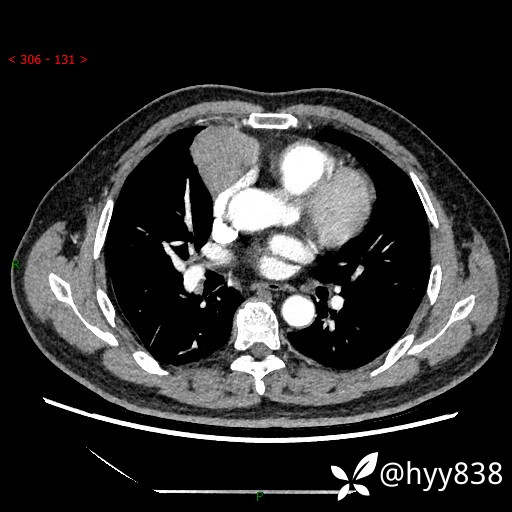

胸部CT平扫

动脉期+静脉期

各期CT值